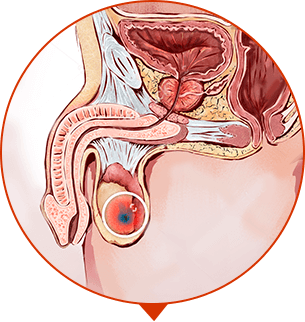

SURUNKALI PROSTATITNI DAVOLASHDA INQILOB

2-QADAM

siydik ajralishi barqarorlashadi, kamayadi, yallig'lanish yo'qoladi

3-QADAM

ereksiya qayta tiklanadi, organizm mustahkamlanadi, prostatit qaytalanmaydi